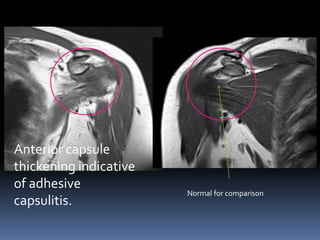

Anterior middle

posterior

Anterior capsule

thickening indicative

of adhesive

capsulitis.

Normal for comparison